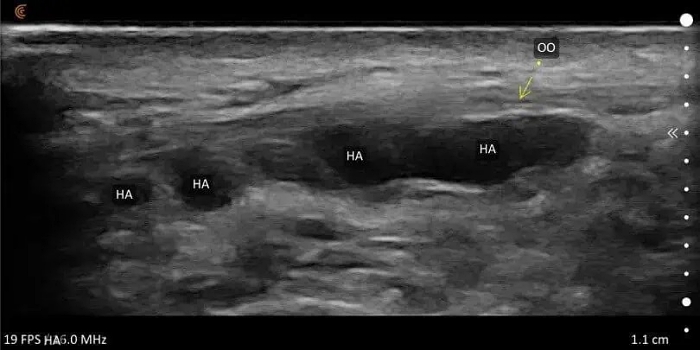

| 填充物種類 | 物質辨識 | 辨識玻尿酸(呈無回音黑區)、脂肪(雜訊團狀)、增生劑(高回音顆粒狀)等不同填充物質。 |

| 深度層次定位 | 精準分層 | 確認填充物位於真皮層、皮下脂肪層、筋膜層或骨膜層等,有利後續處置。 |

| 異物反應/結節 | 病變識別 | 若已產生硬塊、包膜、結節,可辨識出由纖維組織環繞的高回音層,評估反應程度。 |

正常情況下,表皮與真皮在超音波影像上呈現一條連續亮白線,就像地圖上清楚的邊界線,代表皮膚表面完整且健康。脂肪層呈現黑灰交錯的蜂巢狀,中間穿插許多細白線條;那些白線就是 FSN(Fibro-Septal Network,纖維隔網絡),代表皮膚與脂肪之間的關係是「鬆軟又有彈性」。如果看到脂肪小葉之間的纖維隔變得過粗、過亮、呈片狀連續高回音,就要警覺可能有異物反應。

臉部異物反應的超音波示意圖

超音波下看到局部反光很強、亮白一片(高回音)的區塊,代表:纖維化疤痕、過度增生的膠原蛋白、填充物殘留或包膜化。

圖片可見,脂肪層中出現高回音顆粒或片狀反光區,代表膠原增生或纖維化組織形成。這時FSN失去彈性,像被黏死在一起。觸診可摸到硬塊,動態表情「卡卡的」,笑線不順、臉部像被束住。

玻尿酸是目前臨床使用最廣泛的填充物之一,特點是吸水性強、流動性佳,可完全代謝。超音波下的玻尿酸呈現為均勻、清澈的低回音(黑色)區塊,邊界清楚、結構完整。但若注射在錯誤層次過淺或劑量過多,容易發生丁達爾效應(在光線下透藍或灰光)、明顯的水袋感或是整體臉型變得浮腫。

自體脂肪是許多人認為最「天然」的選項,但也可能帶來最難處理的饅化結果之一。當注射量過多、分佈不均或細胞存活率不佳時,壞死的脂肪會被人體吸收、纖維化,最後形成硬塊或疤痕結節。在超音波影像下,這些脂肪殘留或纖維化區塊呈現為亮白片狀的高回音區域,邊界模糊、與周圍組織混合,難以單獨區分。